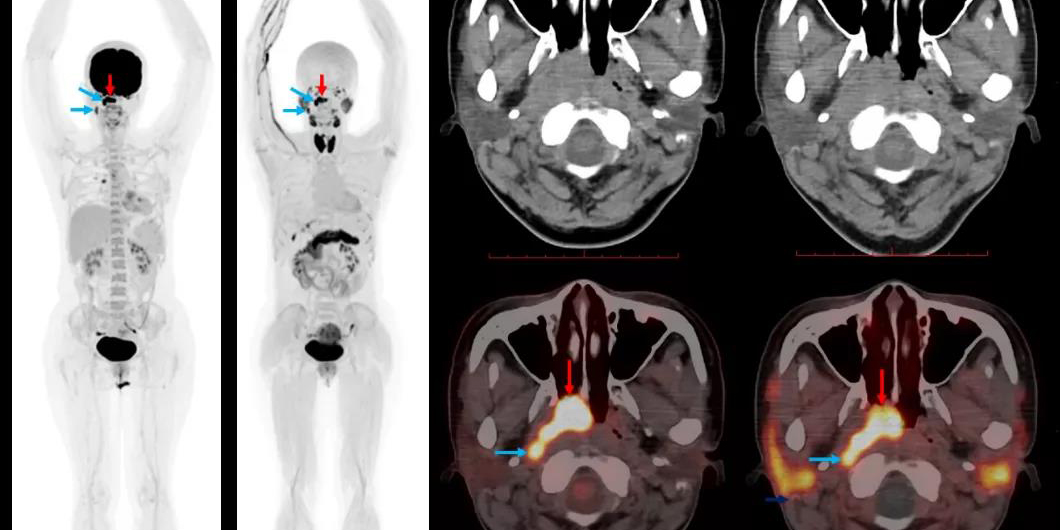

Acta Pharmaceutica Sinica B | 苏金团队参与研制针对纤维化疾病早诊的新型放射性药物